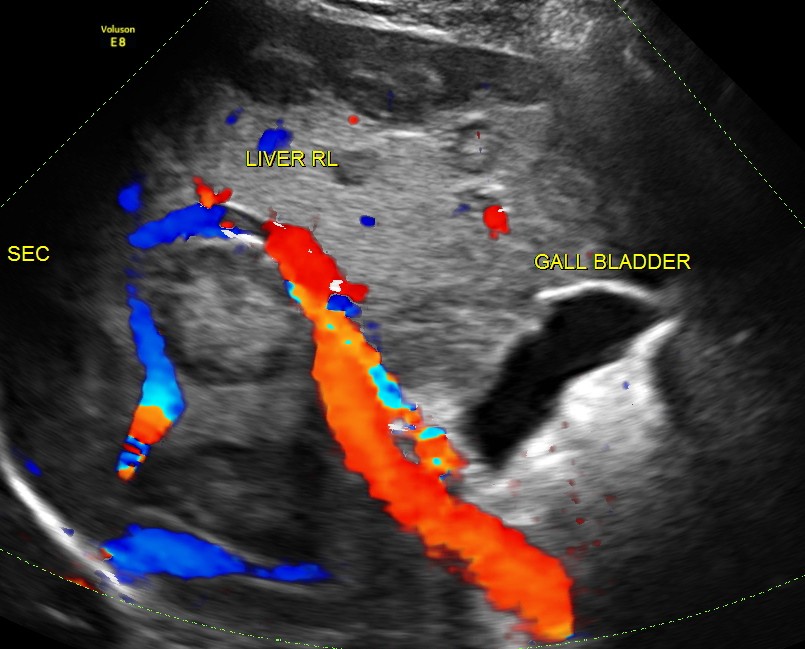

His liver showed multiple secondaries .

secondaries show target appearance or bird’s eye view of mexican hat appearance

The diagnosis offered was multiple liver secondaries with incidental finding of shrunk right kidney with probable reduced function.